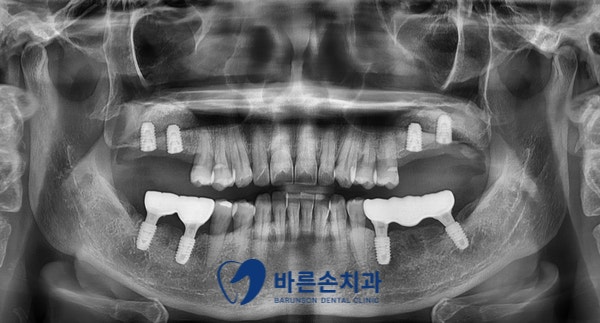

윗 어금니까지 보철물을 완성한 후 파노라마 엑스레이 사진입니다.

아래 어금니들은 발치와 동시에 임플란트 식립을 해서 일찍 완성이 된 모습입니다.

위 어금니들은 임플란트와 상악동 측방 거상술로 뼈 이식을 많이 해서 기다리는 중이고,